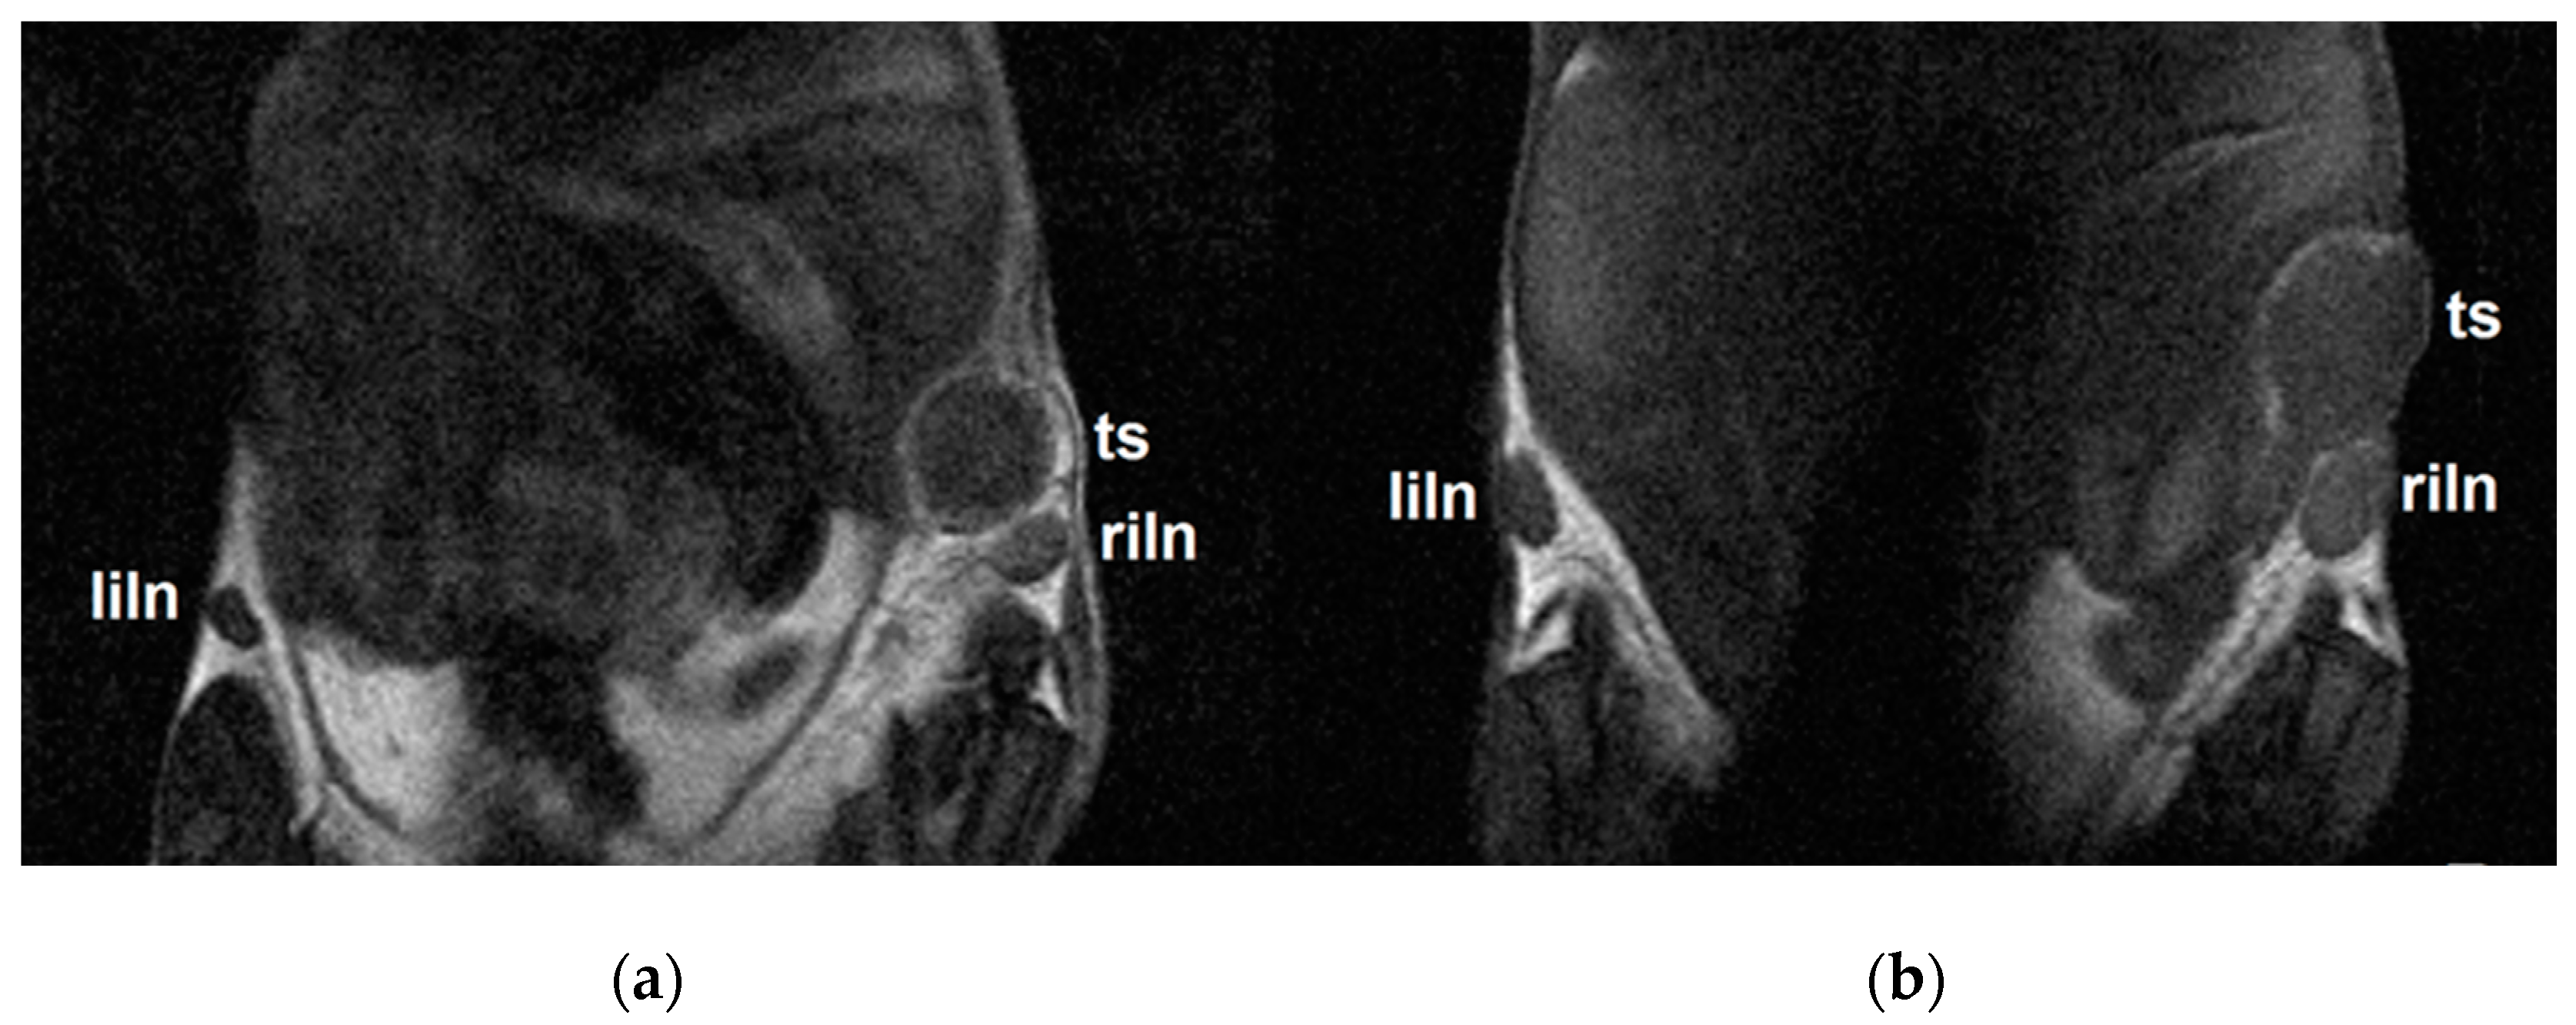

2.6. MRI Results Correlated with Results from In Vivo Fluorescence